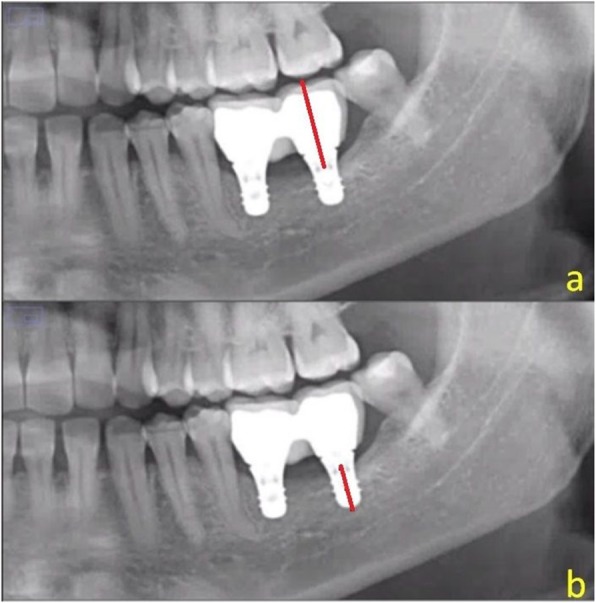

Measurement of the crown-implant ratio

The crown-implant ratio was measured using the ImageJ version 1.38 software measuring tool in conjunction with a magnification tool. Each implant was measured from its bottom to the crown base and then from the crown base to its highest point (Fig. 4).

Fig. 4.

The crown-implant ratio measurement showing a the length of the crown (red line) and b the length of the implant (red line)